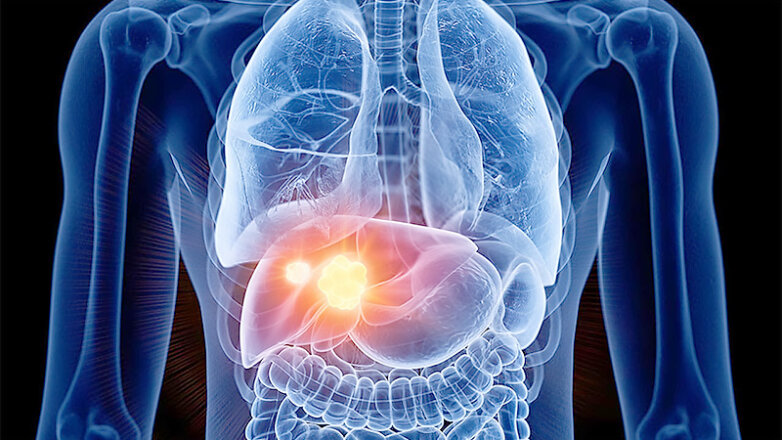

Οι παράγοντες κινδύνου για ηπατοκυτταρικό καρκίνωμα σε ασθενείς με κίρρωση ήπατος

Σε παγκόσμιο επίπεδο, το ηπατοκυτταρικό καρκίνωμα αποτελεί μια κοινή κακοήθεια. Σύμφωνα με τη βάση δεδομένων GLOBOCAN 2020 που συμπεριλαμβάνει στοιχεία από 185 χώρες διεθνώς, το 2020 εκτιμάται ότι 905.700 άνθρωποι διαγνώστηκαν με καρκίνο του ήπατος και 830.200 άνθρωποι πέθαναν από καρκίνο του ήπατος παγκοσμίως. Ο καρκίνος του ήπατος ήταν μεταξύ των τριών συχνότερων αιτιών θανάτου […]